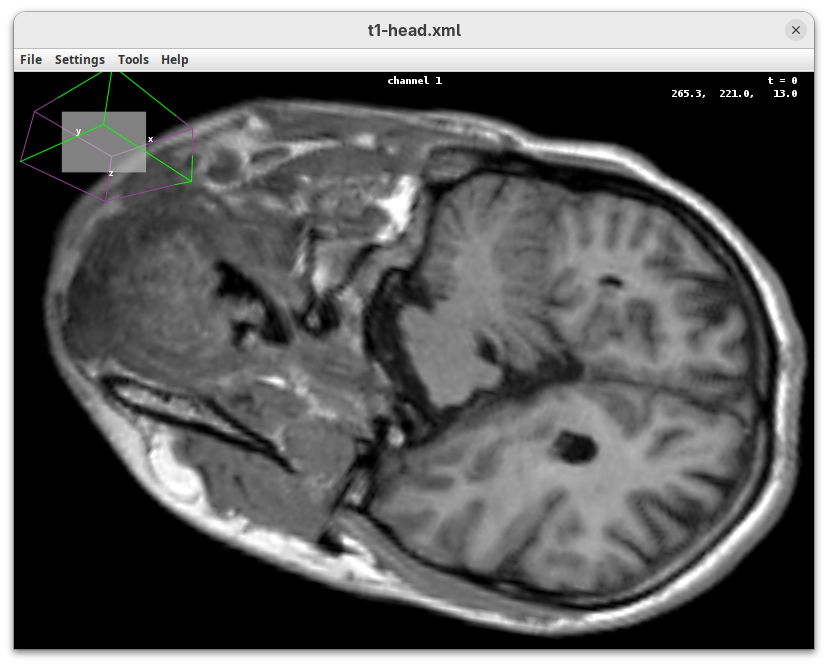

Cropping

Another useful 3Dscript option is the ability to crop the bounding box to show the inside of the sample. We can do it in the XYZ directions or in the near/far axis, defined from the user point of view.

- Set the Z range minimum value to

60(you can also drag the slider) to slice the sample through the Z axis.

- Now rotate the sample to see the cropped region from other angles.

- Set the Y range

minto125and rotate around.

- Finally, reset the position and cropping parameters and set the Near/Far minimum to

0and move the sample around to see the dynamic reslice of the sample with this cropping parameter.

- Reset transformations and cropping parameters.